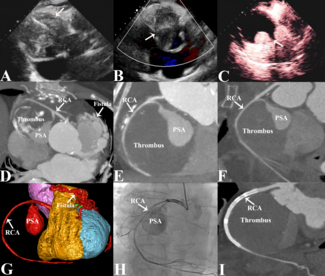

A 76-year-old male with a history of arterial hypertension and hypercholesterolemia, but no known coronary artery disease, presented with typical chest pain. Electrocardiography showed ST-segment elevations in leads II, III, aVF, and V6.